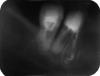

Прилагаю снимок зуба с кистой, это - предпоследний этап лечения, в кисту через каналы введено лекарство (типа жёлтого геля). Мне сказали прийти через полгода с новым снимком, за это время киста в лучшем случае исчезнет.

Посмотрите, пожалуйста, как проведено лечение?